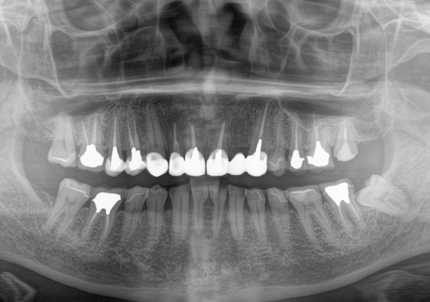

患者:Y.S 様

初診日 :2018年10月

主訴 :上顎前歯部審美障害、臼歯部補綴治療

1.初診時口腔内写真(2018年10月)